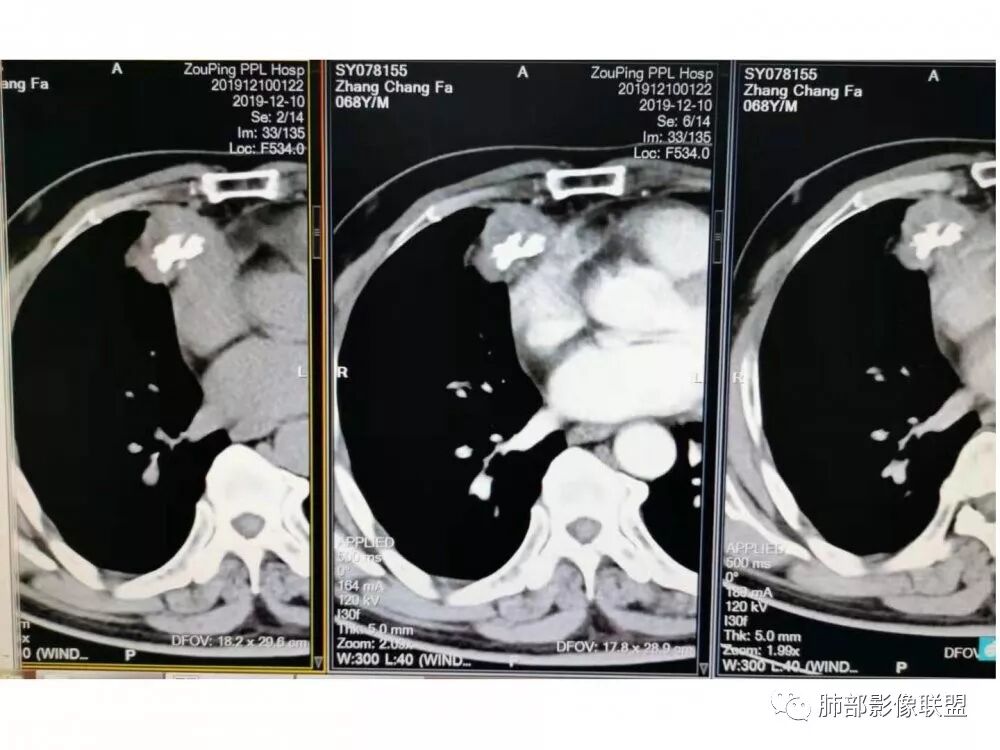

定位:肺内?肺外?

肺侧表面光滑,血管推移

胸膜增厚,朝肺侧稍掀起。

支持肺外

实性部分密度与肌肉类似,钙化粗大、结节状

右侧内乳动脉增粗

实性部分中度强化——增加20~27HU

深分叶,边界尚清,附近未见肿大淋巴结

这是不是胸膜尾不能确定